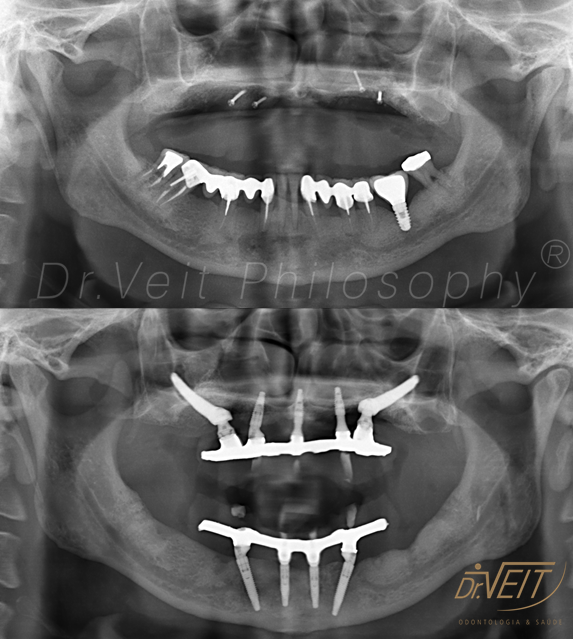

Reabilitação Oral com Implantes Zigomáticos

Arte de reabilitar os casos  “impossíveis”. Pacientes que buscam a reabilitação oral podem conquistar um belo sorriso com segurança, mais conforto e tranquilidade com o uso do Implante Zigomático. A técnica possui o diferencial de realizar a implantação no osso zigomático e é indicada para casos de perda óssea maxilar avançada.